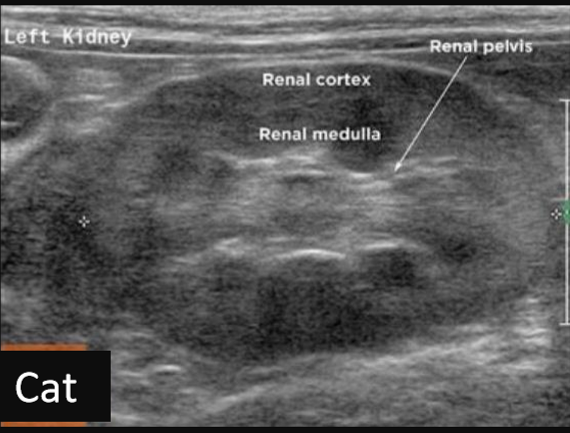

Label this frontal/dorsal kidney ultrasound

A